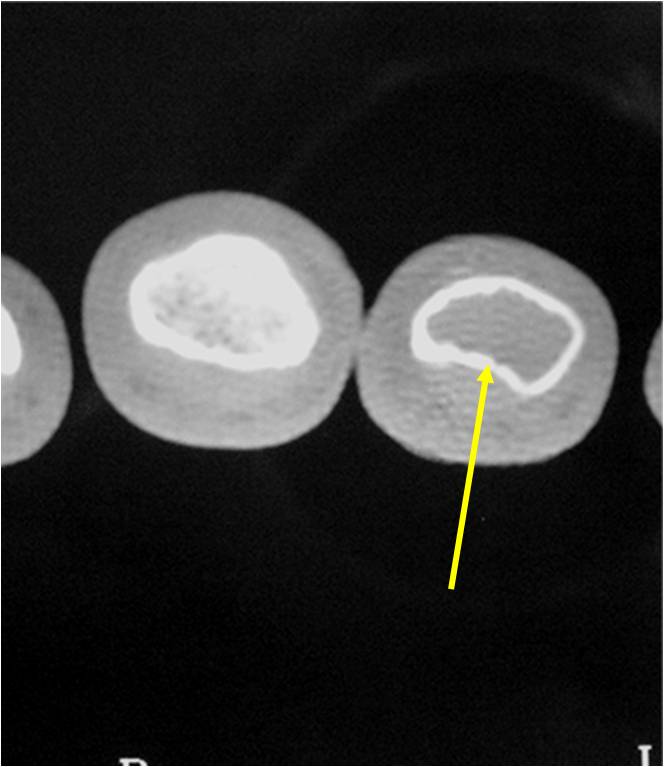

- Endosteal erosion>2/3 cortical thickness on a CT scan